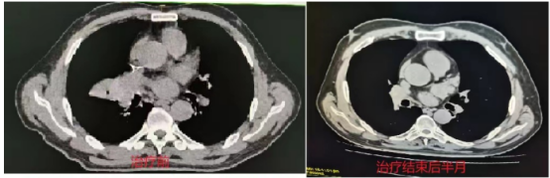

(四)肺癌

行IMRT治疗半程CT图像对比图